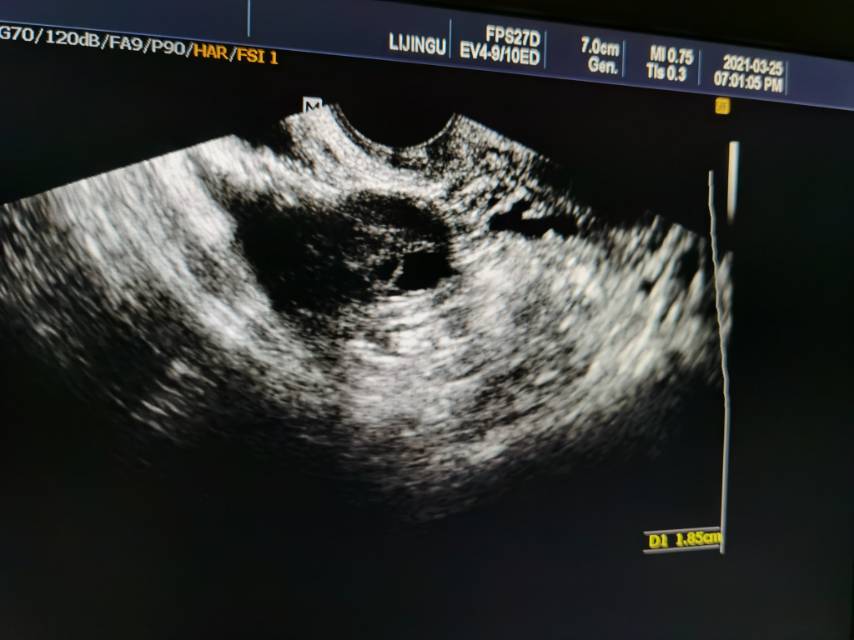

之前做过的性激素六项检查睾酮有点高,身体多毛,超重,备孕半年没有成功,b超有点不典型多囊,卵泡有十个,开始检测卵泡,上个月有优势卵泡但是较扁,成熟时候lh值很低就打了破卵针,结果还是来月经了。

符合多囊卵巢综合征,监测卵泡,如果发育不好,可以促排卵。做胰岛素释放试验+OGTT,是否有胰岛素抵抗。减重。